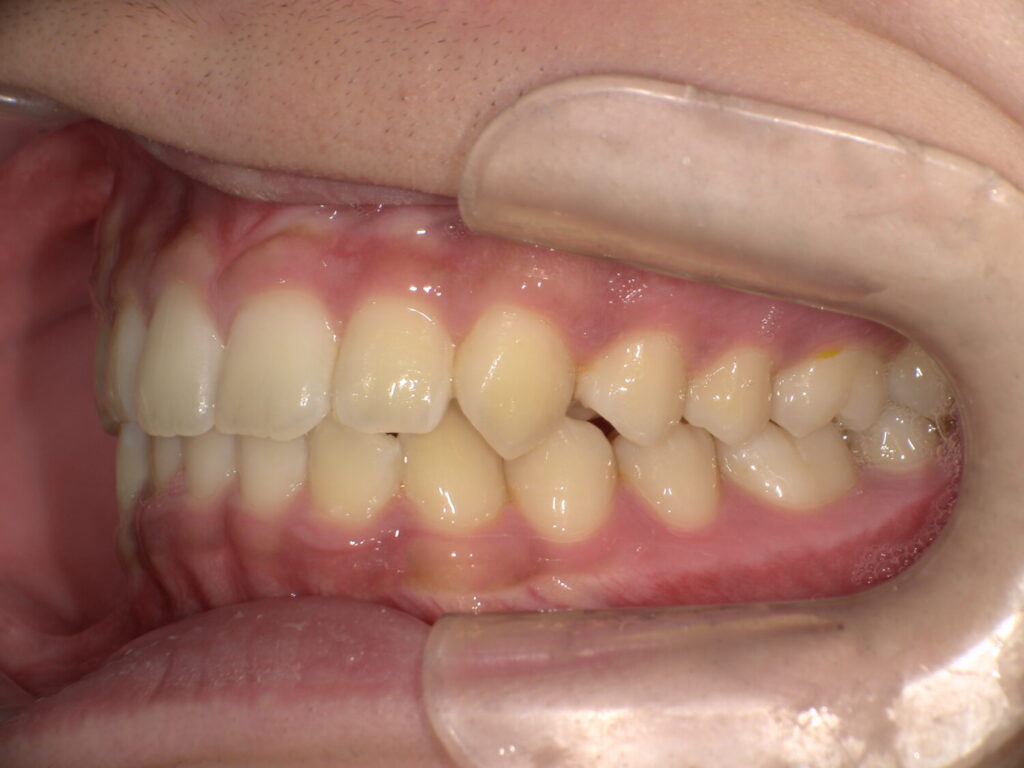

半年後の下の歯の写真です。

がたつきがあったのも綺麗になり、調和の取れた歯並びへ変わってきています!

舌のアクティビティーが少し苦手だったり受験などもあり、3年ほどかかりましたがアクティビティー卒業する頃には綺麗な歯並びになりました!

下の歯もしっかりと見えています。